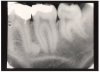

Figure 2 – Bitewing Images

Figure 2

Bitewing examinations were introduced by Dr. Raper in 1925. Bitewing images focus on the clinical crowns of both the maxillary and mandibular teeth. Bitewings do not show the apices of the tooth and cannot be used to diagnose in this area. The greatest value of bitewing radiographic images is the detection of interproximal caries in the early stages of development, before it is clinically apparent. The arrows in Figure 2 indicate areas of interproximal caries. Bitewing images also reveal the size of the pulp chamber and the relative extent to which proximal caries have penetrated.